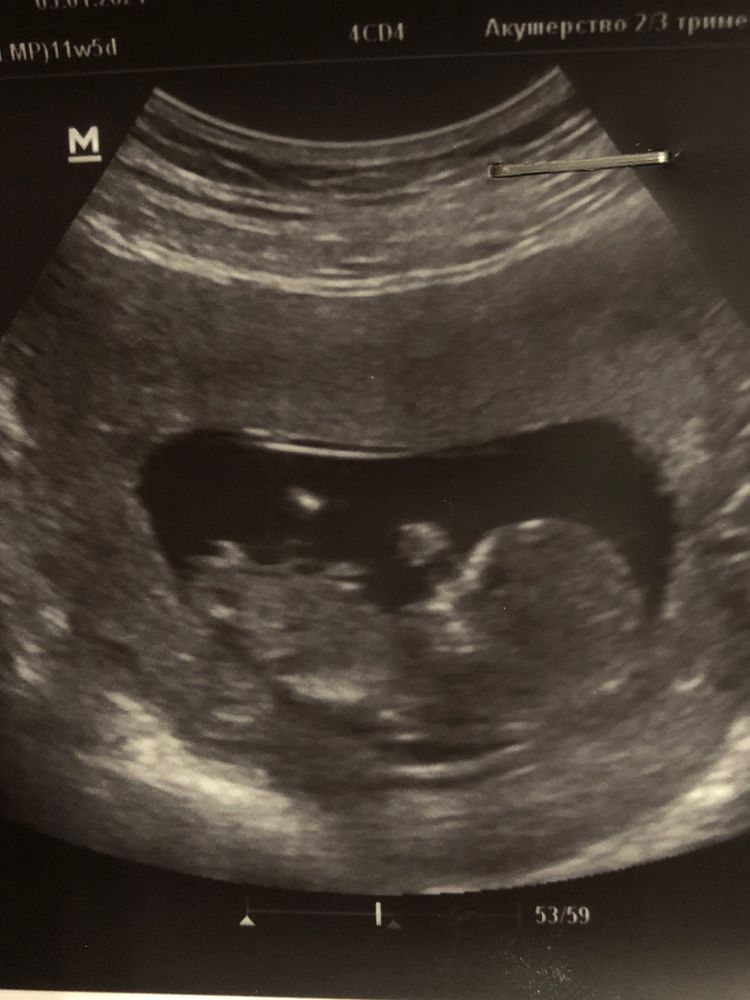

Первый скрининг мальчик или девочка?😍

Я думаю девочка, так как на втором фото половой бугорок параллельно телу. У мальчиков обычно чуть угол другой